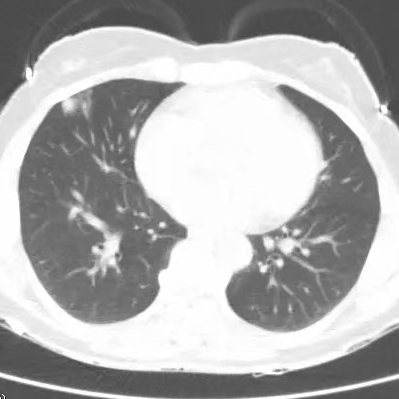

健康直通车: 健康是生命的宝贵财富,也是幸福生活的基石。为了更好地服务广大百姓,传播健康知识,葫芦岛市第二人民医院推出“健康直通车”专题栏目,将专业的医学知识以通俗易懂的方式传递给每一位市民,掌握科学的疾病预防方法,共同构筑健康中国的坚实基石。 什么是肺结节 肺结节是指肺内直径小于或等于3cm的类圆形或不规则形病灶,影像学表现为密度增高的阴影。大于3cm的称肿块。肺结节依其密度不同可分为实性结节、部分实性结节、磨玻璃结节,其中部分实性结节的恶性可能性最大,磨玻璃结节次之,实性结节尤其是小的实性结节结节最可能是良性的。 肺结节的常见病因 1、良性(约90%) 🔸 感染:结核、真菌、细菌性肺炎后遗留的瘢痕; 🔸 非感染:错构瘤(良性肿瘤)、炎性假瘤、血管瘤等。 2、恶性(约10%) 🔸原发性肺癌(如腺癌、鳞癌); 🔸转移性肿瘤(其他器官癌症转移至肺)。 如何根据影像判断肺结节性质 1、依据结节大小判断 🔸小于0.5cm的肺结节绝大多数都是良性的,属于微小结节。即使部分小于0.5cm肺结节是恶性的,但是适当的观察不影响预后。每年复查一次胸部CT就可以。 🔸大于0.5cm持续存在的纯磨玻璃结节,观察6个月,若持续存在,不管有无进展均多数是恶性的,视患者意愿,手术可以立即做也可观察至进展再做,不影响预后。 🔸大于0.8cm的部分实性结节恶性可能性非常大,应积极评估结节边缘毛刺、分叶、胸膜凹陷等征象。 🔸若实性部分大于0.5cm,恶性率显著提高。若在3~6个月随访期间实性部分增大或者总体部分增大,都可以考虑手术切除。而即使小于0.8cm的部分实性结节也需3个月就复查对比。 2、依据肺结节形态 如CT上提示病灶形态不规则、毛刺、分叶、胸膜凹陷、空泡征、血管集束征等,符合恶性肿瘤的征象。 🔸结节与正常肺组织之间界限非常清楚的恶性可能性大。 🔸结节密度不均呈混杂密度或均匀较大纯磨玻璃结节也基本是恶性的。 🔸有胸膜牵拉(不管是肺表面的脏层胸膜还是叶间裂部位的胸膜)的恶性可能性大。 🔸结节有浅分叶、细毛刺,密度较高而与周围肺组织边界不清的恶性可能性大。 🔸磨玻璃或混合磨玻璃结节存在小空洞的恶性可能性大。 🔸影像上似慢性炎表现,而没有炎症相关的其他异常,特别当所谓炎症区域内部或一侧与正常肺组织之间界限非常清楚的基本上是恶性的。 3、从结节发展情况来看 所有随访中增大进展的都需要考虑恶性可能,不进展而持续存在的纯磨玻璃结节也需考虑恶性。 葫芦岛市第二人民医院肺结节诊治中心孙振教授深耕肺结节领域四十余载,凭借对临床实践的执着钻研与深厚积淀,在肺结节精准诊断及鉴别诊断领域形成独到见解。他系统总结海量临床病例,创新性提炼出一套科学化、规范化的肺结节全周期诊疗体系,尤其在早期微小结节的影像特征识别、良恶性风险分层等方面积累了丰富经验,为众多患者提供了精准、高效的诊疗方案。 人民医院·人民名医 孙振 主任医师 三级教授 ·葫芦岛市第二人民医院胸外科主任、肺结节诊治中心主任 ·中国医科大学客座教授 ·原央企总医院著名胸外科专家 ·辽宁省医学会胸外科委员 ·辽宁省抗癌协会肺癌专业委员会委员 ·辽宁省细胞生物学学会食管癌专业委员会理事 ·主持多项科研成果获科技成果奖、科技进步奖、国家专科奖项 医学成就 从事胸外科临床工作近40年,担任胸外科首席专家及科室主任20余年,是我省胸外科领军人物,推动肺癌、食管癌等胸部肿瘤外科的规范化诊疗,在央企总医院牵头成立了肺结节诊疗中心,率先开展CT引导下肺内小结节定位切除,既确切完整切除肺内小结节,又降低肺功能损害。 专业特色 擅长肺癌、食管癌的外科手术和综合治疗,在各类高难度胸外伤手术治疗、胸腔镜微创手术、胸腺瘤手术及复杂并发症处理方面具有高深造诣,尤其擅长肺癌早期诊断,胸部小结节CT早期肺癌的鉴别等。完成各类高难度胸外科手术5000余例,其中微创手术占比达90%,治愈率达98%,多项业务填补省内空白。 开展的高难手术 胸腔镜肺部结节微创手术、肺癌根治术、食管癌根治术、各种纵隔肿瘤切除术、胸骨后甲状腺手术及胸部复合性外伤的抢救手术等。